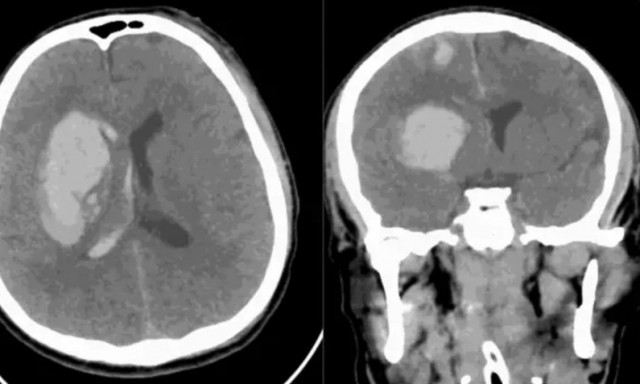

Η πιο πρόσφατη καταγεγραμμένη περίπτωση αφορά έναν 34χρονο άνδρα στα Ηνωμένα Αραβικά Εμιράτα, ο οποίος μολύνθηκε από τον μύκητα τρεις μήνες μετά από σοβαρό τροχαίο και νοσηλεία σε ΜΕΘ. Παρά τη φαρμακευτική αγωγή και τα χειρουργεία, η λοίμωξη προχώρησε έως και τον εγκέφαλο, με την Candida auris να αποδεικνύεται εξαιρετικά ανθεκτική.